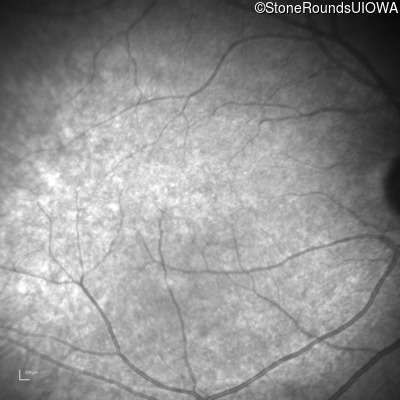

Congenital Stationary Synaptic Dysfunction (IA2g)

Congenital Stationary Synaptic Dysfunction (IA2g)

| Congenital Stationary Synaptic Dysfunction | CABP4 | Arg49Stop CGA>TGA | IVS1+1 G>T | AR |